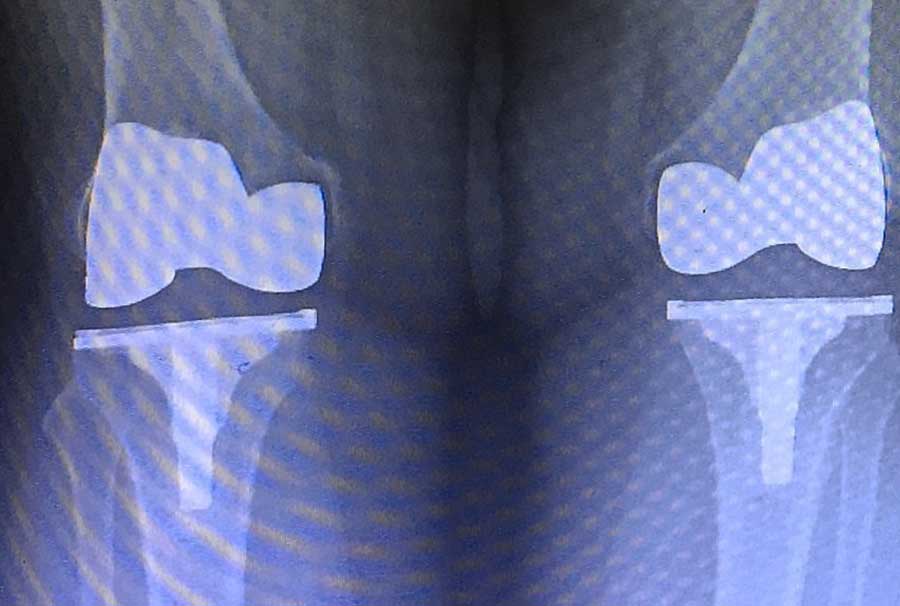

Pullig’e göre, eğer implantların protezlere uygulanabilir bir alternatif olduğu kanıtlanırsa, kıkırdak dejenerasyonunun tedavisinde devrim yaratacak. Şimdiye kadar terapötik yaklaşımlar ağrı yönetimi veya yapay eklem değişimi ile sınırlıydı. Dünya çapında 500 milyondan fazla kişi diz eklemindeki artritin ağrılı ve zayıflatıcı etkilerinden muzdarip. Obezite oranları artmaya devam ettikçe ve ortalama yaşam süresi arttıkça bu yaygın hastalığın yaygınlığı da artıyor.